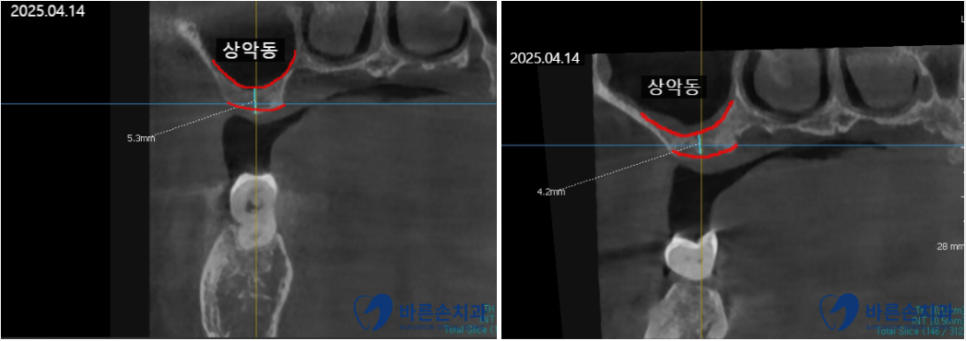

촬영일 2025.04.14

임플란트 계획을 세우기 위해 CT 촬영을 했는데요,

양쪽 위에 어금니쪽 뼈가 너무 얇은 상태라서

임플란트를 심기 위해서는 상악동 거상술이 필요합니다.

임플란트를 심으려면 뼈가 8~10mm 정도 있어야 하는데

현재 상태는 4~5mm 밖에 없네요..ㅠㅠ

<상악동 거상술 + 뼈이식>

코 옆, 광대 뒷쪽에 위치한 뼈 속 빈 공간 ‘상악동’이라고 합니다.

뼈의 두께가 얇으면 상악동을 들어올려서 빈 공간에 뼈이식을 함으로써

임플란트를 심을 수 있는 뼈의 두께를 만드는 술식입니다.